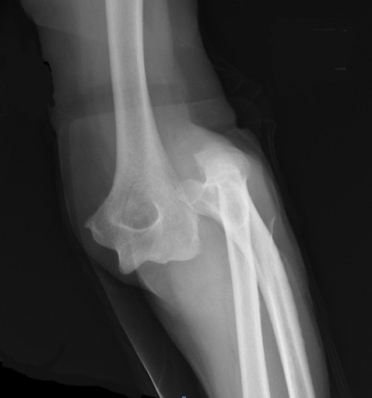

What’s the Diagnosis? Gepost op 2 december 20182 december 2018 door netwerkvsseh What’s the Diagnosis? @emdaily.cooperhealth.org Dit delen: Delen op X (Opent in een nieuw venster) X Share op Facebook (Opent in een nieuw venster) Facebook Delen op LinkedIn (Opent in een nieuw venster) LinkedIn E-mail een link naar een vriend (Opent in een nieuw venster) E-mail Afdrukken (Opent in een nieuw venster) Print Vind-ik-leuk Aan het laden... Gerelateerd